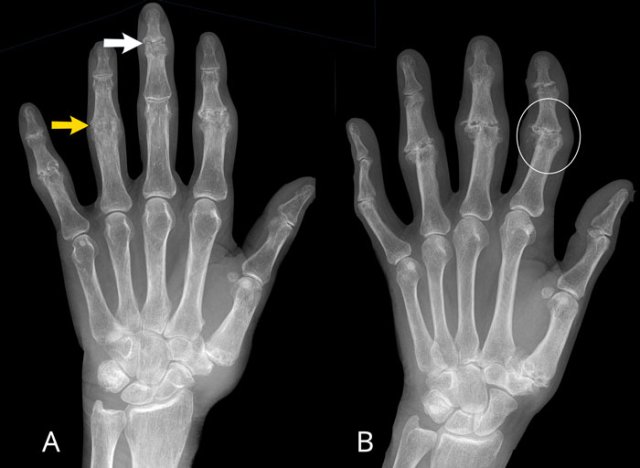

Erosive osteoarthritis in two patients Erosive osteoarthritis in two patients

A

Erosive changes of PIP 2-5 and DIP 3-5.

Typical gullwing deformity in DIP 3 (white arrow).

Ankylosing of PIP 4 (yellow arrow), which occurs in a late phase of the disease.

B

Joint space narrowing with central erosions. Gullwing deformity of PIP 2-4, DIP 2 and CMC-1 joint.

Ankylosing of DIP 3. Medial deviation of PIP 2.

Ball catcher view of the hands in a patient with erosive osteoarthritis.

There is bilateral extensive damage to the IP joints.

Note the symmetrical distribution and sparing of the MCP joints.

Typical gull-wing appearance of the DIP-joints, also known as seagull erosions or sawtooth appearance.

This is classically seen in erosive osteoarthritis, but has also been reported in psoriatic and rheumatoid arthritis.